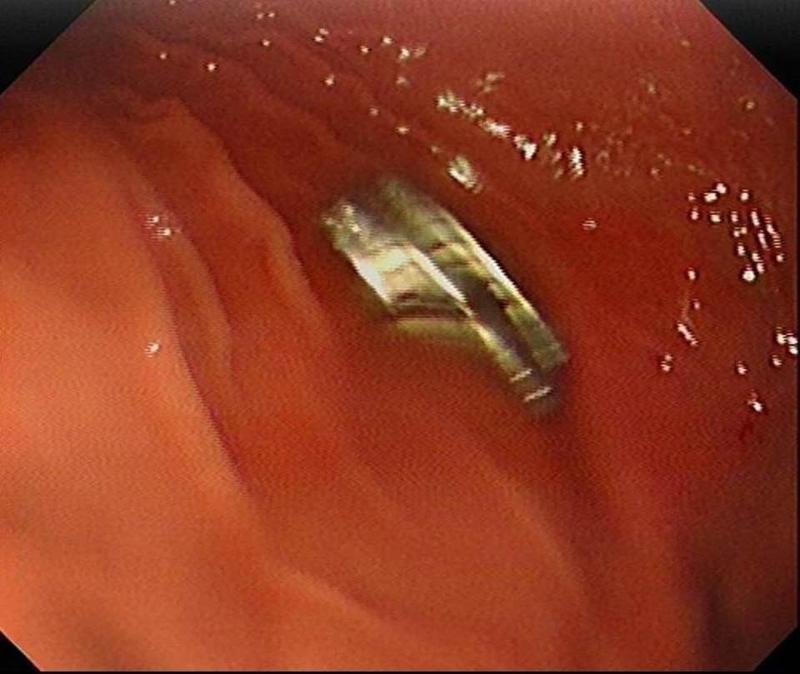

Edinilen bilgiye göre, Erzurum'da bir çocuk evde bulunan 19 tane mıknatısı yuttu. Çocuğun rahatsızlanması sonucu durumu öğrenen aile hastaneye başvurdu. Daha sonra çocuk Elazığ'a sevk edildi.

3 YAŞINDAKİ ÇOCUĞUN BOĞAZINDAN 19 TANE MIKNATIS ÇIKARTILDIFırat Üniversitesi Çocuk Gastroenteroloji Hepatoloji ve Beslenme Bilim Dalı Başkanı Prof. Dr. Yaşar Doğan, çocuk hastanın yemek borusuna yapışmış 19 mıknatısı endoskopik yöntemle çıkardı.

Mıknatıslar uzun süre yemek borusunda takılı kaldığı için yemek borusu ve mide girişinde zedelenmeler olurken, çocuğun sağlık durumunun iyi olduğu ve taburcu edildiği öğrenildi.